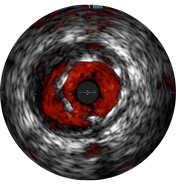

На мальаппозицию указывает наличие крови за стратами стента. При визуализации с использованием режима ChromaFlo кровоток окрашен в красный цвет для простого выявления мальаппозиции и других особенностей просвета.

• Простая оценка аппозиции стента, размера просвета и других показателей за счет выделения кровотока красным цветом одним нажатием кнопки.